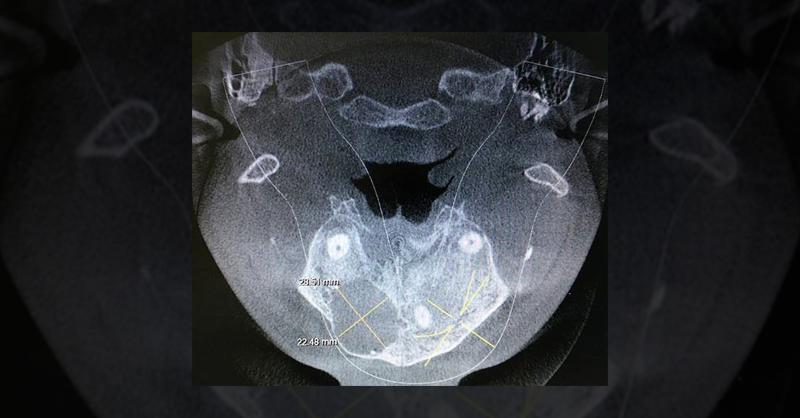

A 24-year-old male with swelling in the upper right tooth region underwent CBCT following referral. Physical examination noted voice resonance and occasional headaches. CBCT revealed a large unicystic radiolucency spanning from the periapical area of 13 to the periapex of 16, accompanied by the absence of the left maxillary sinus. Axial imaging del